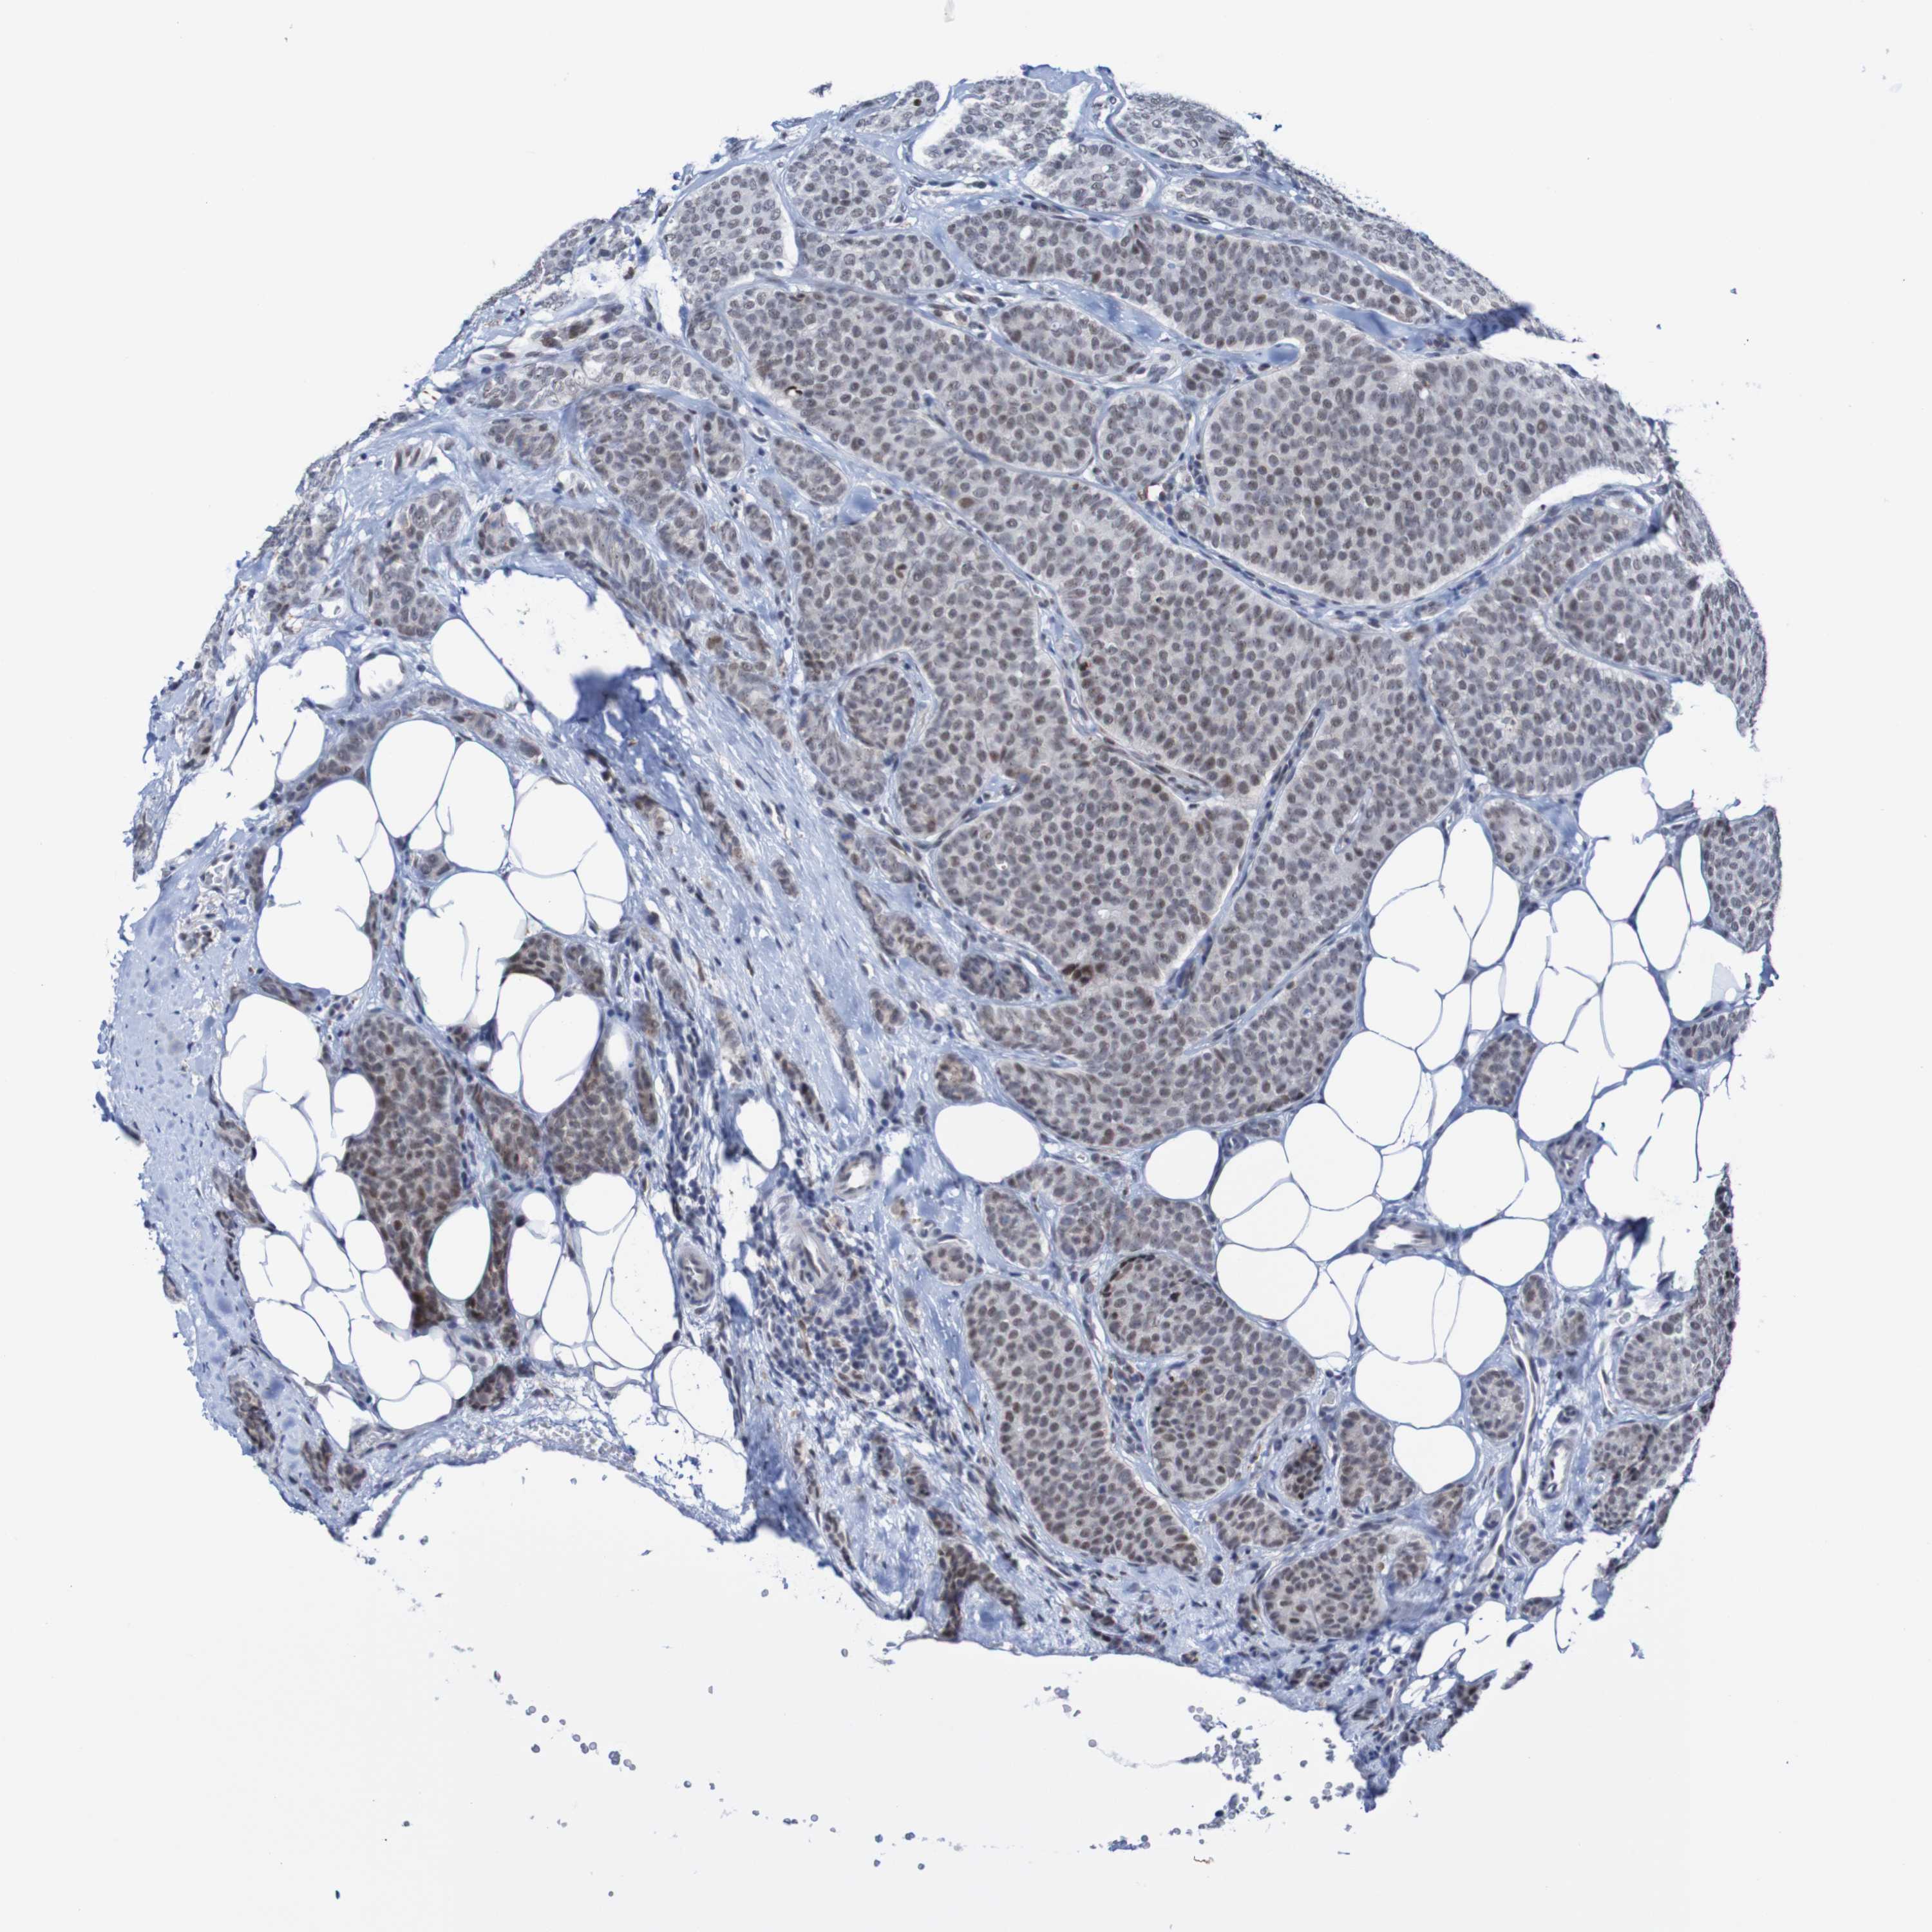

CANCER BREAST CANCER Show tissue menu

BRCA TCGA BRCA VALIDATION PROTEIN EXPRESSION